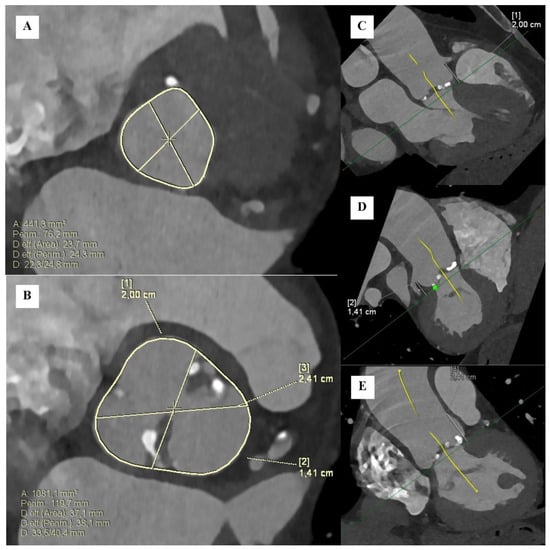

- Guzzetti, E.; Simard, L.; Clisson, M.; Clavel, M.-A. Multiplanar “En Face” Reconstruction of the Aortic Valve. JACC Cardiovasc. Imaging 2020, 13, 2678–2680. [Google Scholar] [CrossRef]

- Pawade, T.; Sheth, T.; Guzzetti, E.; Dweck, M.R.; Clavel, M.A. Why and How to Measure Aortic Valve Calcification in Patients with Aortic Stenosis. JACC Cardiovasc. Imaging 2019, 12, 1835–1848. [Google Scholar] [CrossRef]